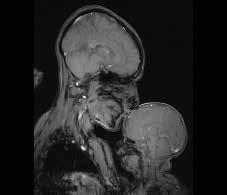

“Pel que fa a mi, vaig veure una imatge molt antiga renovada. La Mare i el Nen és un poderós símbol d’amor i innocència, bellesa i fertilitat. Tot i que aquests valors materns, i les dones que els encarnen, poden ser venerats, generalment se’ls veu en oposició a altres valors: investigació i intel·lecte, progrés i poder.

Però sóc neurocientífica i vaig treballar per crear aquesta imatge, i a la vegada sóc la mare que apareix a la imatge, arraulida dins el tub amb el meu fill petit... “.

Dra. Rebecca Saxe. Neurocientífica del Departament de Ciències Cognitives i Cerebrals de l’Institut de Tecnologia de Massachussets.

A l’abril de 2015, Rebecca Saxe, neurocientífica del Departament de Ciències Cognitives i Cerebrals de l’Institut de Tecnologia de Massachussets (MIT per les inicials del seu nom en anglès, Massachussets Institute of Technology), ens regalava una imatge commovedora que donaria la volta al món en tan sols uns minuts.

Aquesta ressonància magnètica que captura la imatge de la Dra. Saxe amb el seu nadó de tan sols pocs mesos de vida traspassa els límits de la ciència i desentranya la universalitat de dues figures amb la seva roba, cabell i rostre invisibles, que podrien ser qualsevol mare amb el seu fill, en qualsevol moment o lloc de la història.

La seva genialitat rau no només en la seva capacitat de posar en evidència les clares diferències anatòmiques entre el cervell d’un adult i el d’un nen en ple desenvolupament de les seves capacitats, sinó que a més és una finestra que deixa al descobert “l’anatomia del vincle” en tot el seu esplendor més enllà de tota individualitat i revela el nexe d’unió que hi ha entre tots dos estadis evolutius del desenvolupament cerebral: l’amor i les cures d’una mare cap al seu fill. Perquè la mare, a través de les seves carícies i dels seus petons, del joc, de la parla, l’alimentació i l’estimulació tàctil, olfactiva i visual que li proporciona el seu nadó durant els primers mesos de vida, exerceix un potent estímul que prepara al cervell immadur del seu fill per a que aquest pugui desenvolupar més endavant tot el potencial per al qual està genèticament determinat.